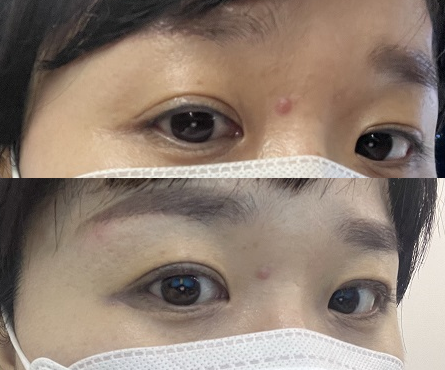

좌/우로 뒤집어 보시면 라인이 남아있지만 점막이 가까울수록 남아있어요 ㅜㅜ

많이 사라진 줄 알았는데 리뷰를 찾을 때 레이저하면 색소를 올려서 더 진하게 보일지도 모른다는 말이 생각났더니 ㅅ왼쪽 눈은 색이 조금 옅어진 정도? 오른쪽과 달랐다.

좌/우 그래서 이날은 눈 감고 찍어볼래 ㅎㅎ 셀카 힘들겠다 라인이 그만 올라가라는 거야 ㅠㅠ 오른쪽이 진하게 보이는 이유는 피코지…

역시 남는건 비포아 후타 ㅋㅋㅋㅋㅋㅋㅋㅋㅋㅋㅋㅋㅋㅋㅋㅋㅋㅋㅋㅋㅋㅋㅋㅋㅋㅋㅋㅋㅋㅋㅋㅋㅋㅋㅋㅋㅋㅋㅋㅋㅋㅋㅋㅋㅋㅋㅋㅋㅋㅋㅋㅋㅋㅋㅋㅋㅋㅋㅋㅋㅋㅋㅋㅋㅋㅋㅋㅋㅋㅋㅋㅋㅋㅋㅋㅋㅋㅋㅋㅋㅋㅋㅋㅋㅋㅋㅋㅋㅋㅋㅋㅋㅋㅋㅋㅋㅋㅋㅋㅋㅋㅋㅋㅋㅋㅋㅋㅋㅋㅋㅋㅋㅋㅋㅋㅋㅋㅋㅋㅋㅋㅋㅋㅋㅋㅋㅋㅋㅋㅋㅋㅋㅋㅋㅋㅋㅋㅋㅋㅋㅋㅋㅋㅋㅋㅋㅋㅋㅋㅋ

아이라인 문신 제거 일주일 후반기 끝!